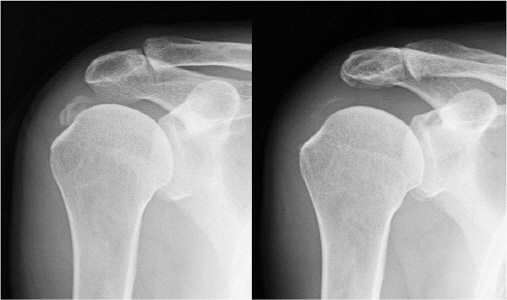

석회화건염은 어깨의 건(힘줄)부분에 석회질이 쌓이는 것이다. 평소에 별 다른 징후가 없다가 갑자기 어깨가 아프다면 석회화건염을 의심해 볼 수 있다.

이 질환의 정확한 발병 원인은 아직까지 정확히 밝혀지지는 않았지만, 노화에 따른 어깨 힘줄의 퇴행 등이 원인으로 알려져 있다. 다른 어깨질환들과는 다르게 처음 석화가 생성되는 시기에는 어깨가 뻐근할 뿐 통증이 거의 나타나지 않는다. 하지만 점차 석회가 커지면서 통증도 심해지고 팔의 움직임이 제한되는 게 특징이다. 이를 방치할 경우 자칫 만성통증이 되어 잘 낫지 않거나 심할 경우 힘줄이 파열될 수 있다.